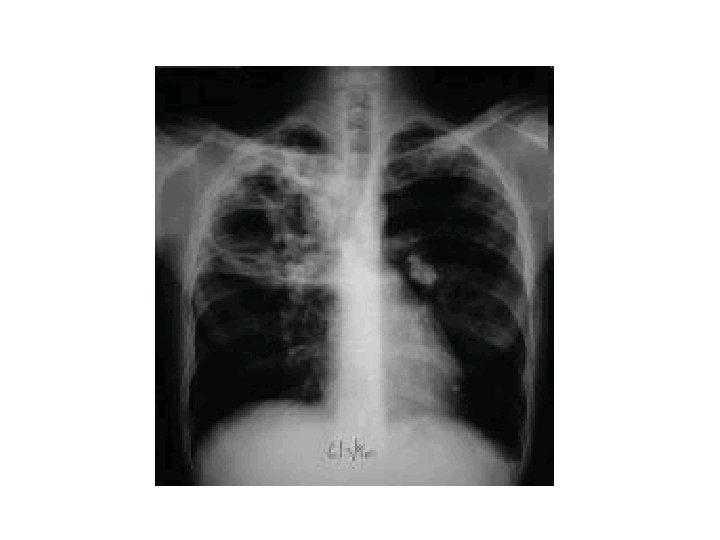

Diagnosis • Obtain HIV in all patients with TB • CXR – – – may show a patchy nodular infiltrate upper-lobe involvement is most common in any part of the lung cavity: indicates advanced infection • high bacterial load • Miliary TB: appearance of numerous small nodular lesions that resemble millet seeds on CXR